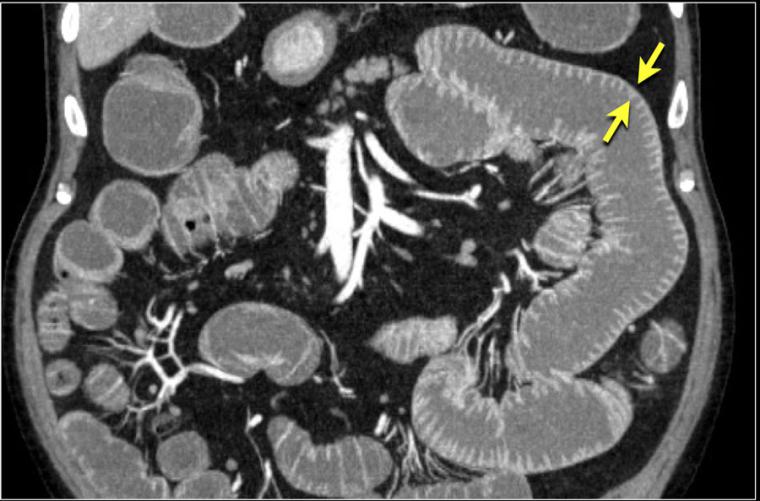

Rektum, genellikle üç ana bölümden oluşur: üst rektum, orta rektum ve alt rektum. Üst rektum, sigmoid kolon ile birleştiği yerdir, orta rektum ise dışkının depolandığı alanı temsil eder. Alt rektum, anüsle bağlantı kuran kısmıdır. Bu bölümlerin sağlıklı işlevi, dışkılama kontrolü açısından kritik öneme sahiptir.

Rektum neresidir? Rektum, kalınbağırsak sisteminin üçüncü bölümüdür. Sigmoid kolon ile anüs arasında yer alır ve yaklaşık 11-12 cm uzunluğundadır. Anüs ile birleştiği alan, koksig kemiğinin 3 cm önünde bulunur. Rektumun üst, orta ve alt olmak üzere üç bölümü vardır.